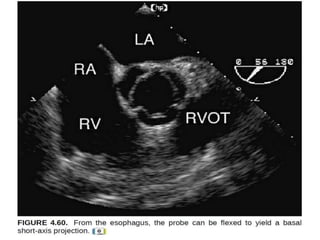

A useful starting point is the four-chamber view, which

is recorded with-

The transducer positioned immediately superior and

posterior to the left atrium and flexed in a way to provide

a long-axis plane through all 4 chambers